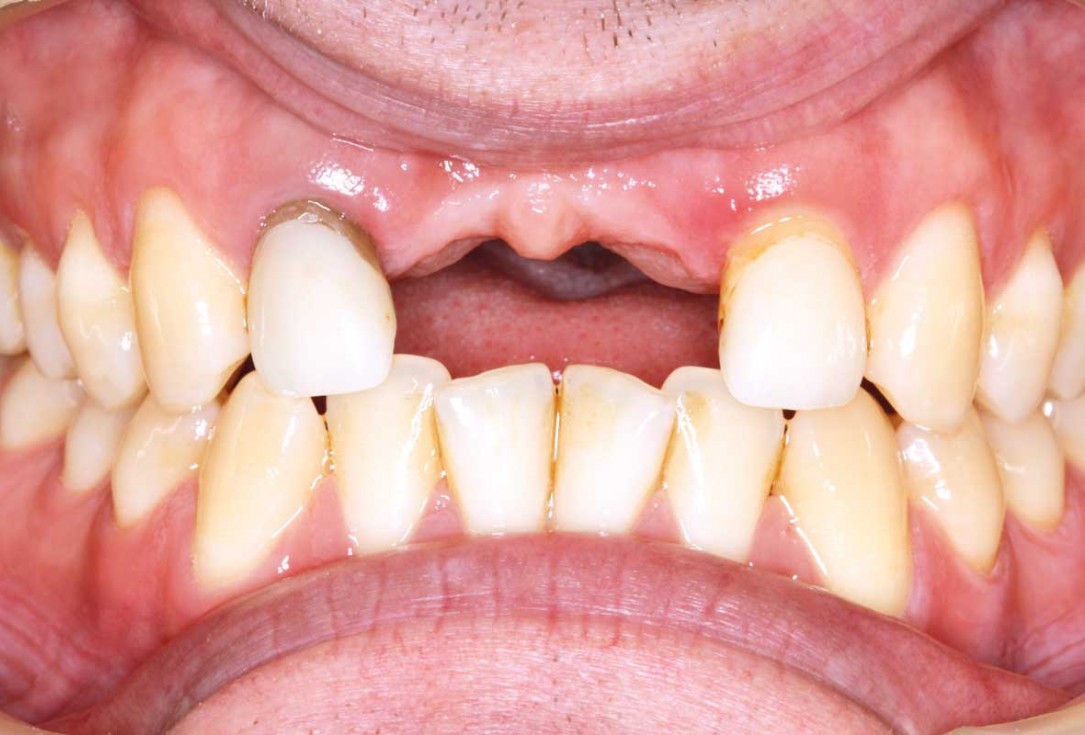

12/26 - Clinical situation after 6 months

Ridge augmentation in the maxilla with maxgraft® bonebuilder in the aesthetic zone - Dr. M. Kristensen